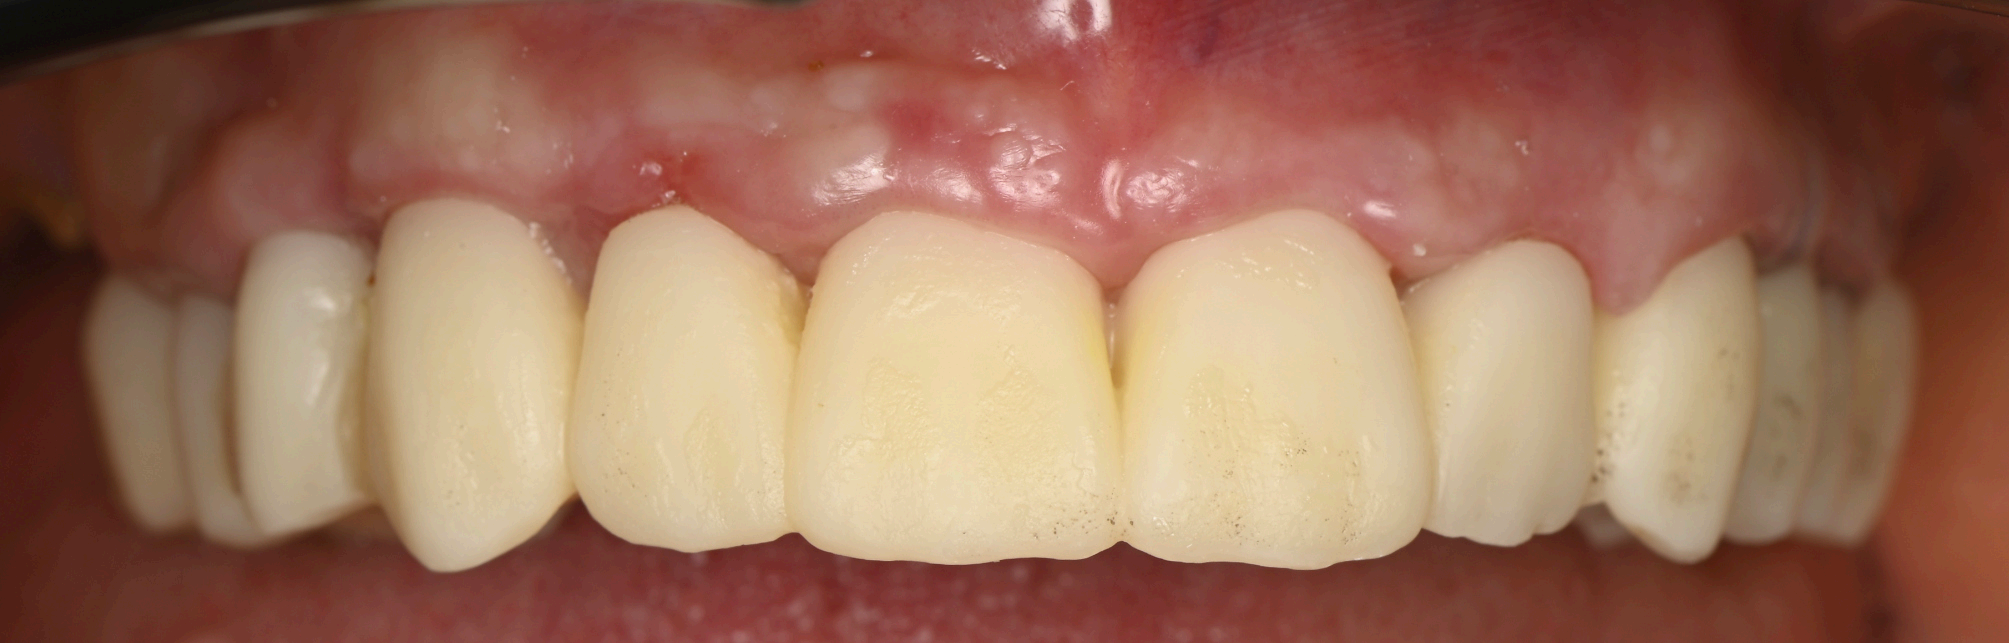

Group 7: Final Prosthesis Fig. 7.1: Final FP1 prosthesis in situ, showcasing aesthetic gingival integration. Fig. 7.2: Translucent zirconia hybrid prosthesis prior to insertion. Fig. 7.3: Zirconia prosthesis with embedded iBar pre-insertion. Fig. 7.4: iBar design process in Blender4Dental.

At three months post-surgery, the soft tissues exhibited a mature, festooned contour that enhanced the aesthetic integration of the prosthesis (Fig. 6.1, 6.2). The refned provisional had successfully guided this outcome, with the gingival margins aligning seamlessly with the prosthetic teeth (Fig. 6.3–6.6). The fnal zirconia-iBar prosthesis demonstrated excellent stability, with no signs of mechanical complications or peri-implant infammation (Fig. 7.1). Aesthetically, the restoration fulflled the patient’s expectations, achieving a natural smile with balanced proportions and a lifelike gingival appearance. Functionally, the patient reported full satisfaction with mastication and speech, indicating a successful rehabilitation.

The fnal prosthesis was designed as a hybrid structure, combining a translucent zirconia framework with a metallic iBar for strength and durability (Fig. 7.2, 7.3). The iBar was modeled in Blender4Dental, optimizing its geometry to distribute occlusal forces across the six implants (Fig. 7.4). The zirconia component was milled to achieve a natural translucency, mimicking the optical properties of natural teeth. After fabrication, the prosthesis was inserted, secured to the MUAs via screw retention, and adjusted to ensure proper occlusion and patient comfort (Fig. 7.1). The fnal design adhered to FP1 principles, replacing only the dental crowns while harmonizing with the scalloped gingival profle established during healing.